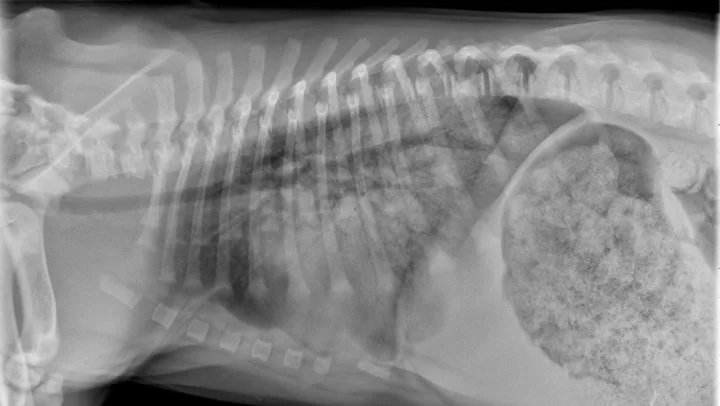

Eosinophilic bronchopneumopathy (EB) is an idiopathic inflammatory hypersensitivity disorder associated with acute onset coughing, gagging, retching, and/or respiratory distress. Radiographs may reveal a diffuse bronchointerstitial pattern or alveolar disease (Figure 3). Patients with EB have airway cytology supportive of eosinophilic inflammation and are negative for parasitic testing.

FIGURE 3

Eosinophilic bronchopneumopathy. Note the heavy, patchy bronchointerstitial pattern.